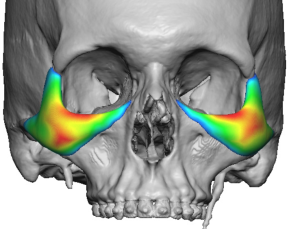

Shape and Surface Characteristics

Contouring

- Fully customized based on CT anatomy

- Accounts for asymmetry, rim depth, and globe position

Feathered Edges

- Minimize palpability and visibility

- Especially important along inferior and lateral borders

Thickness Gradient

- Maximum thickness at the infraorbital–cheek junction

- Gradual tapering medially, laterally, and inferiorly

Design Variations by Severity

Mild NOV

- Rim-focused implant

- Minimal cheek extension

Moderate NOV

- Rim plus cheek extension

- Moderate inferior/maxillary extension

Severe NOV

- Full upper midface wraparound design

- Strong cheek augmentation

- Lateral arch extension

- Greater inferior maxillary expansion